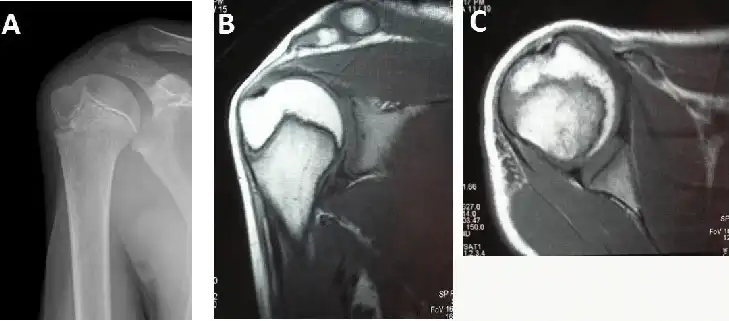

تشخیص دررفتگی شانه: معاینه فیزیکی و تصویربرداری

چگونه میتوان مطمئن شد که شانه دررفته است؟

برای تشخیص دررفتگی شانه، پزشک ابتدا یک معاینه فیزیکی کامل انجام میدهد. در این معاینه، پزشک به شانهی آسیب دیده نگاه میکند، آن را لمس میکند، و دامنهی حرکتی آن را بررسی میکند. همچنین، پزشک ممکن است از شما سوالاتی در مورد نحوهی آسیب دیدگی و علائم شما بپرسد.

برای تأیید تشخیص و بررسی آسیبهای احتمالی دیگر، پزشک ممکن است از روشهای تصویربرداری مانند:

- رادیوگرافی (اشعه ایکس): این روش میتواند شکستگی استخوانها و دررفتگی مفصل را نشان دهد.

- ام آر آی (MRI): این روش میتواند آسیب به بافتهای نرم مانند رباطها، عضلات، و تاندونها را نشان دهد.